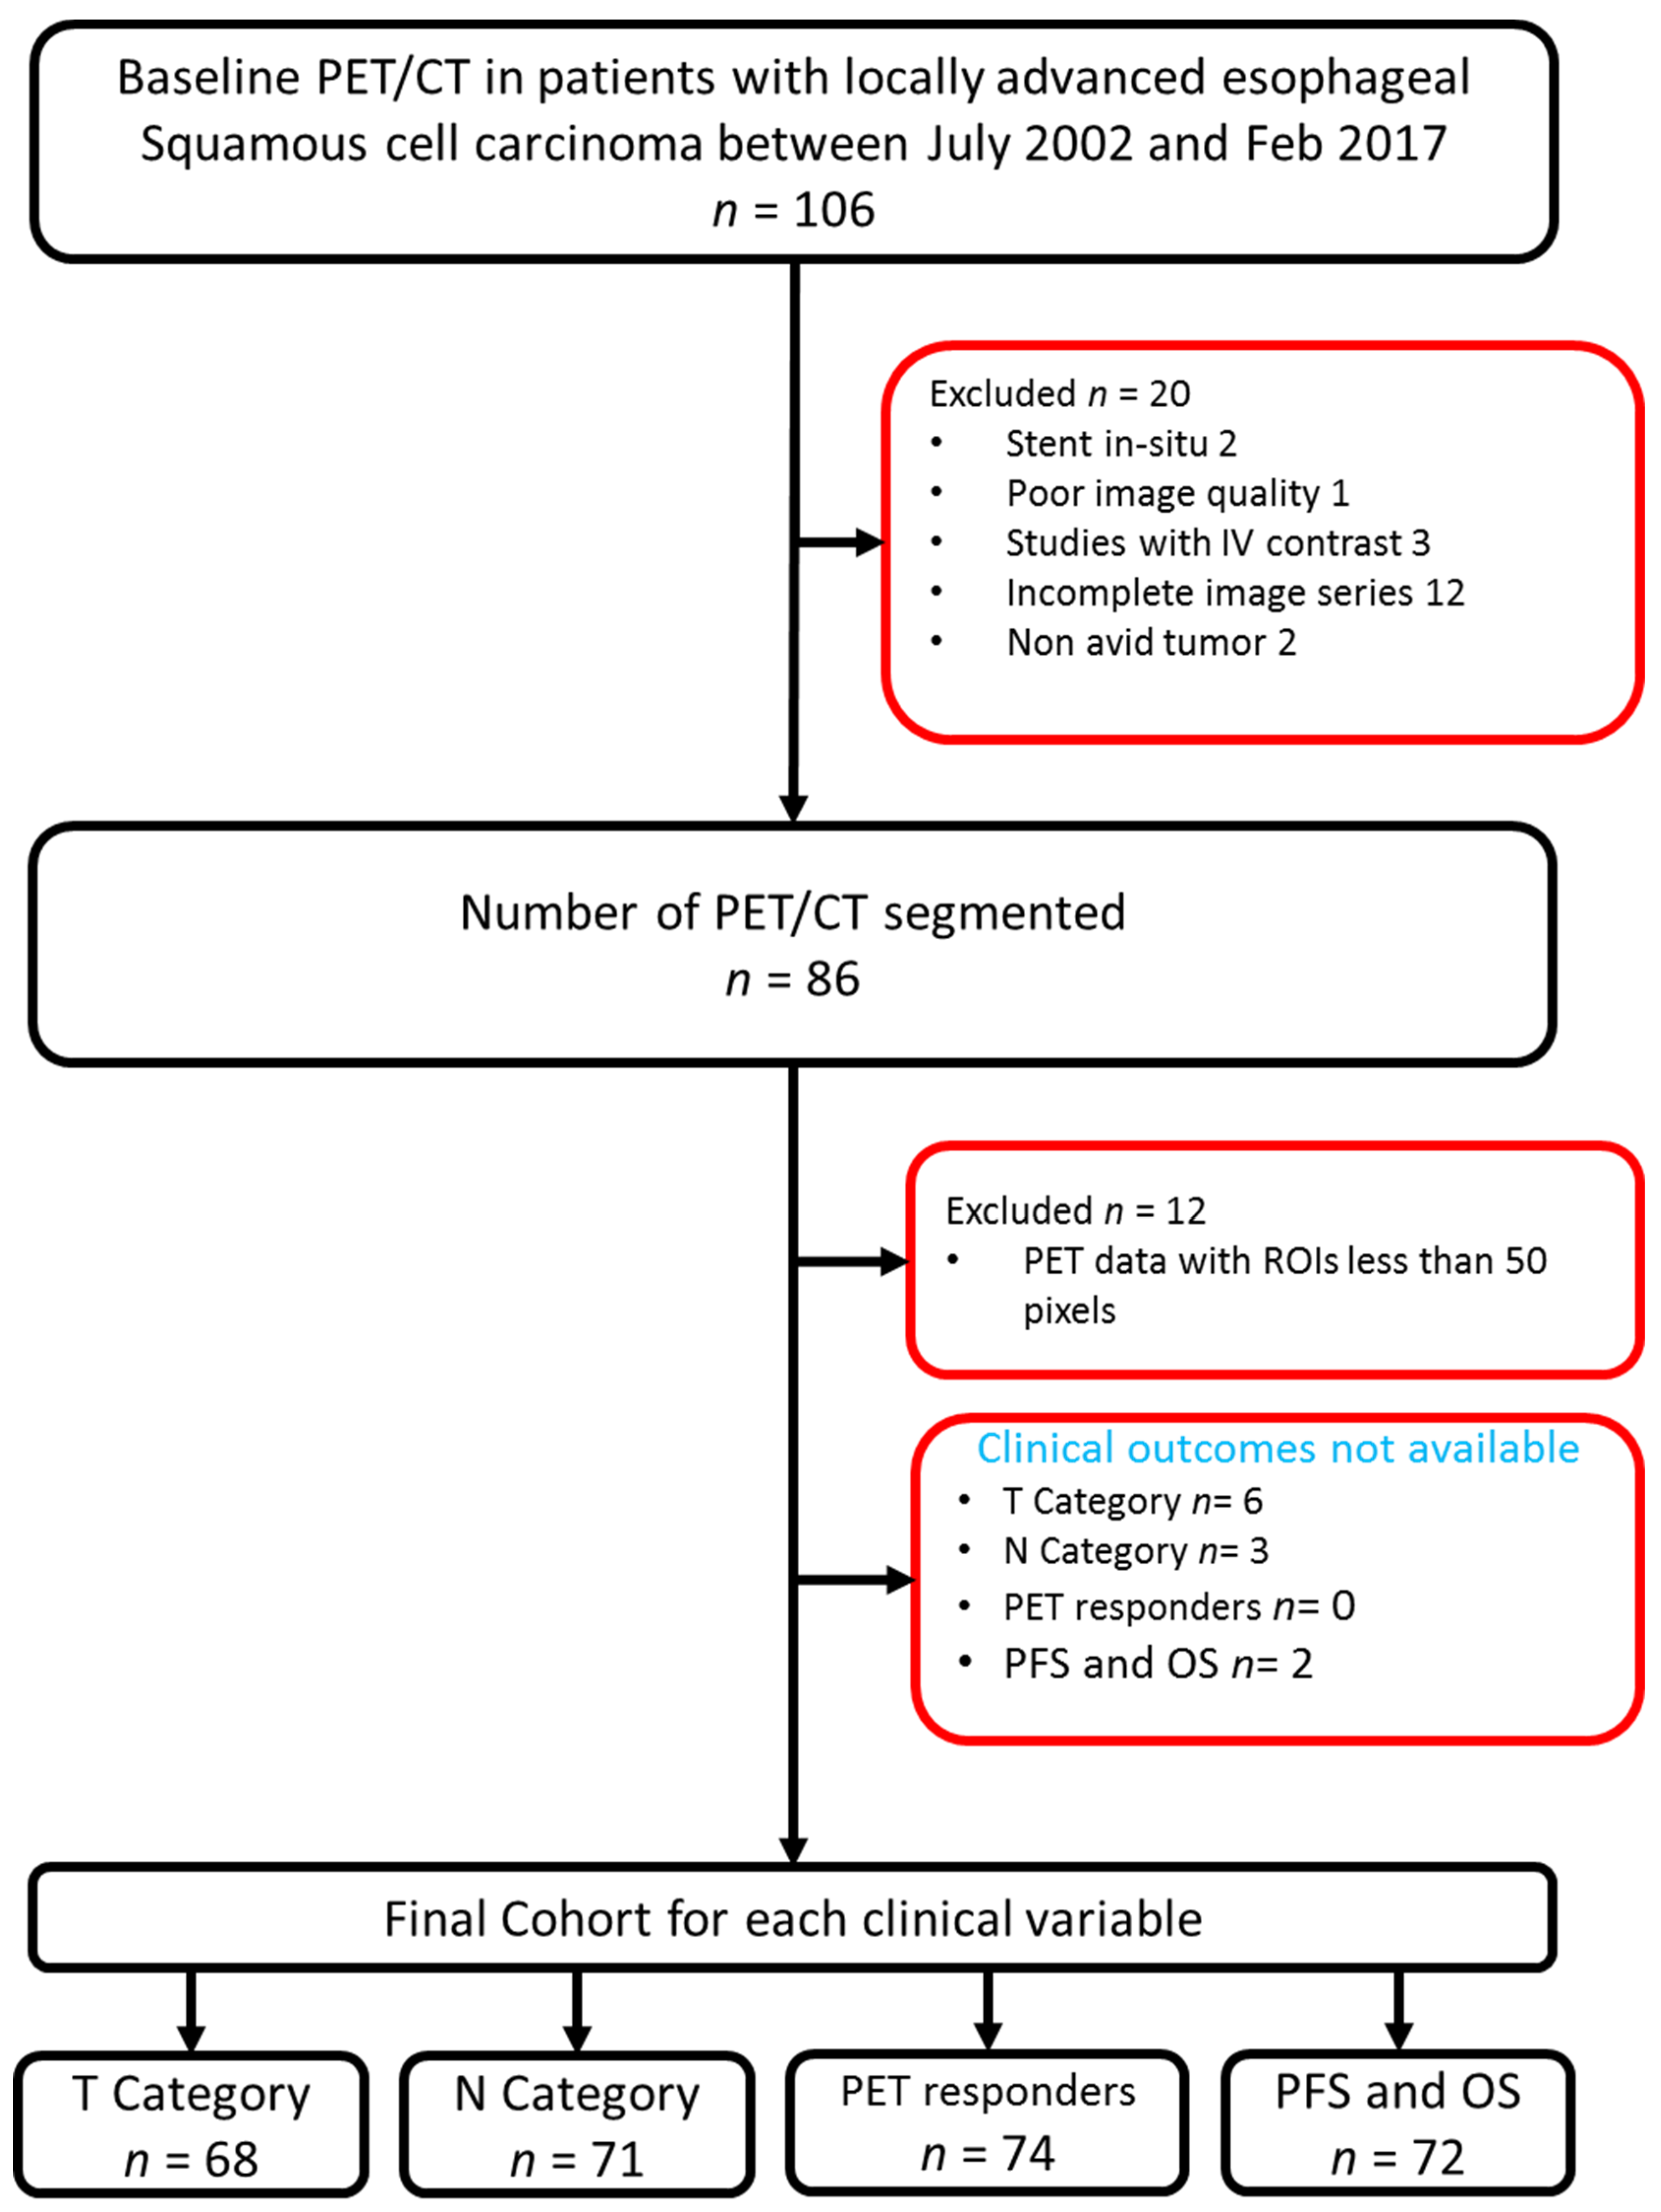

2.1. Patient Inclusion

2.2. Treatment and Imaging

2.3. Image Acquisition and Segmentation

3.1. Patient Characteristics